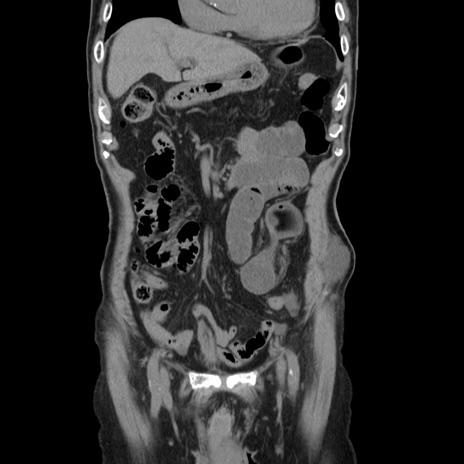

症例24(冠状断像)

【症例】80歳代男性

【主訴】左側腹部痛、嘔吐

【現病歴】本日早朝より左腹部に痛みあり。昼頃嘔吐認めたため、救急要請。

【既往歴】直腸癌(Mile手術)、胆摘

【身体所見】意識清明、BT 35.9℃、BP 221/93mmHg、SpO2 97%(RA) 、腹部:左ストーマ周囲に限局性の腹部膨隆あり。 膨隆部自発痛・圧痛あり・軟。

【データ】WBC 7700、CRP 0.09